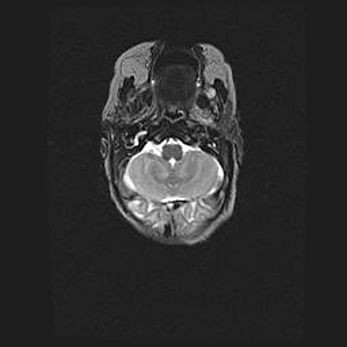

Мальформация Денди-Уокера. Киста задней черепной ямки.

Агенезия мозолистого тела.

Возраст: 2,5 месяца

Вес: 2420 г

Пол: женский

Окружность головы: 37 см

Срок гестации: 32 недели

Мальформация Денди—Уокера — редкий вид патологии ЦНС, представляющий собой врожденный порок развития каудального отдела ствола и червя мозжечка, ведущий к неполному раскрытию срединной (Мажанди) и латеральных (Лушка) апертур IV желудочка мозга. Для этогно синдрома характерна триада симптомов: гипотрофия червя мозжечка и/или полушарий мозжечка, кисты задней черепной ямки, гидроцефалия различной степени. В 70% случаев порок сочетается и с другими аномалиями головного мозга, в частности с агенезией мозолистого тела.